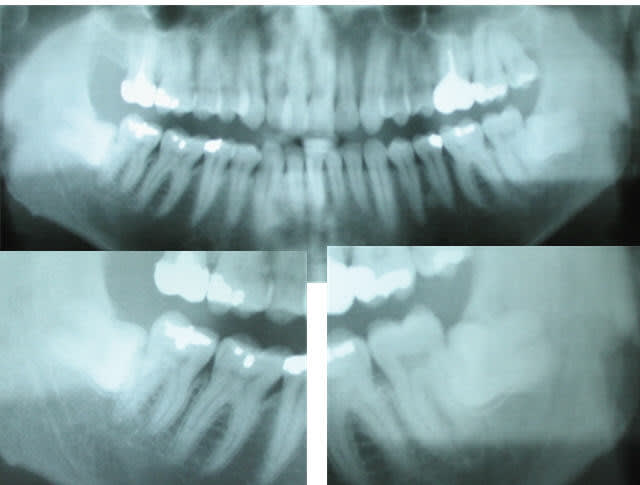

Ce patient, 35 ans , hémophile, porteur de prothèses des genoux doit se faire opérer dans un mois pour en changer une. Il vient avec une OPG et une lettre du service orthopédique:

Par contre, pour les 38 et 48, je lui conseille quoi ?

38 et 48...incluses...aucun symptôme clinique???

y'a pas une carie mésiale sur la 16 ??

T'as bien sondé en distal des 7 du bas car à priori la barrière muqueuse doit être fine.

c'est difficile de proposer une indication prophylactique.

si y'a jamais eu de symptômes sur ces deux 8 je laisse tranquille jusqu'au jour où ça merde.

dans ton compte-rendu précise bien qu'il y a deux dents incluses asymptomatiques sur le plan clinique et radiologique au moment de la consultation et précise que ces dents nécessitent une surveillance.